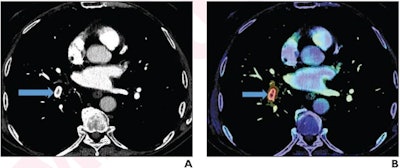

Timely intervention is needed to produce optimal outcomes in patients with acute pulmonary embolus. Batra's team explored whether an AI-enabled worklist prioritization tool could help streamline the imaging process.

The group conducted a study that included 2,501 examinations in 2,197 patients with pulmonary embolism; of these, 1,166 were from the pre-AI period and 1,335 examinations from the post-AI period. The team found that using the algorithm shortened CTPA report turnaround time and exam wait time for routine studies compared to not using it. There was, however, no significant difference in reading time for CTPA reports positive for acute pulmonary embolus, compared with reports from before AI implementation.

Using AI with CTPA could translate to earlier interventions for acute pulmonary embolus.

"By assisting radiologists in providing rapid diagnoses, the AI tool could potentially enable earlier interventions for acute PE," the team concluded.